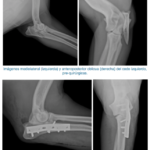

Deformidad de la tibia, causada por una fractura no tratada.

Deformidad de la tibia, causada por una fractura no tratada. Imagen post-quirúrgica, tras alineación de los fragmentos y estabilización con una placa bloqueada.